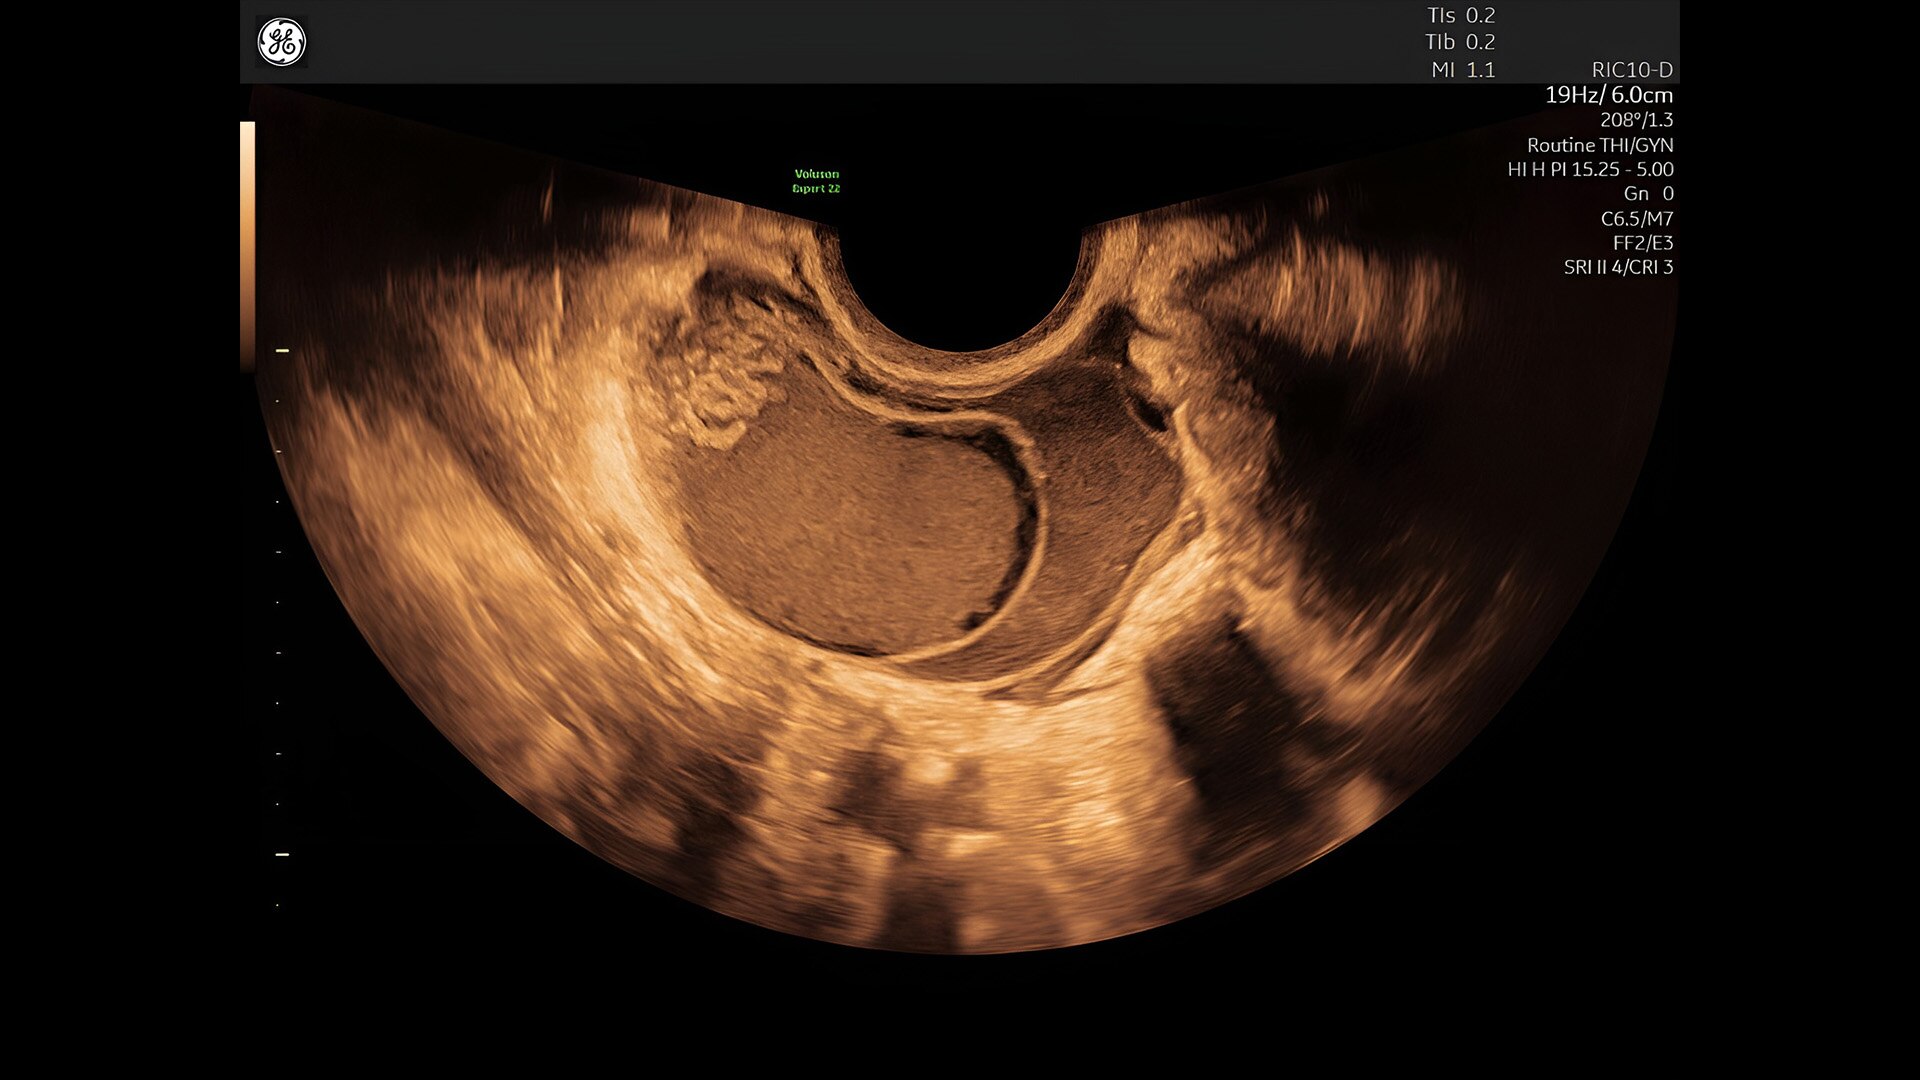

Discover complicated anomalies and pathologies with the Voluson Expert 22 to provide answers sooner for better decision making.

First trimester exams

Perform detailed exams with high-resolution for early insights to fetal health